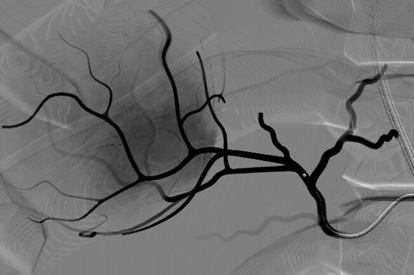

Peripheral Embolization Module

Embolotherapy (HCC & UFE) Module

Prostatic Artery Embolization Module

Advanced Embolization Module